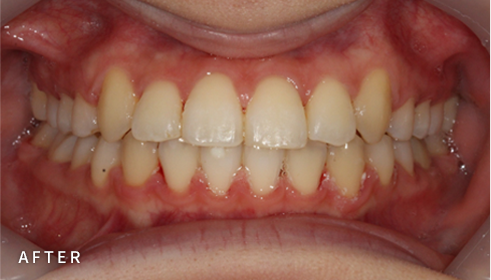

설측교정은 치아 안쪽(설측면)에 초소형 장치로 보이지 않게

아름다운 미소를 만드는 고난이도 프리미엄 교정 치료입니다.

난이도가 높은 만큼 풍부한 진료 경험이 중요합니다.

강남에서 다년간 설측교정에 특화된 경험을 바탕으로,

3D 디지털 기술을 활용한 맞춤 설계, IDBS방식을 통한

정밀하고 불편감 없는 치료를 제공합니다.